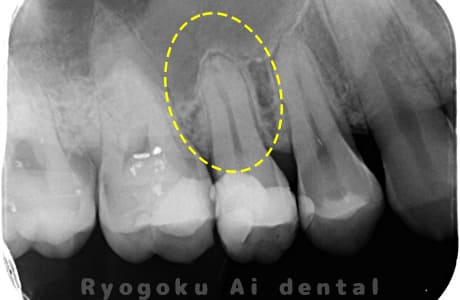

Case02

- 慢性根尖性歯周炎

- 治療期間

-

- マイクロエンド

- 治療費用

噛むと痛みが出る、とのことで来院した患者様です。他院での根管治療を終えてましたが、根尖病変を認めるため、マイクロエンドを行いました。